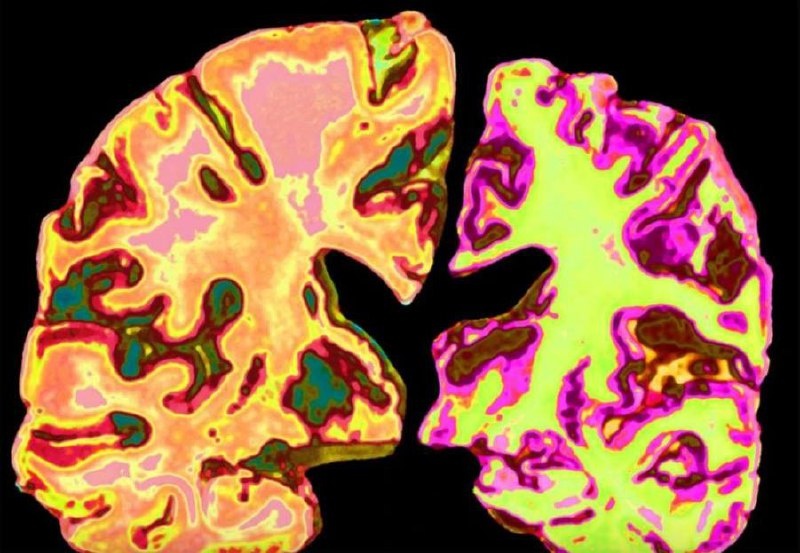

Ученые УНИЧТОЖИЛИ болезнь Альцгеймера — они смогли даже восстановить утраченные воспоминания. Выяснилось, что одна из главных причин ухудшения памяти — низкий уровень лития в мозге. Но это не все: литий работает как профилактика и может навсегда защитить от Альцгеймера. Дальше — клинические испытания и запуск массового производства лекарства.

Ученые УНИЧТОЖИЛИ болезнь Альцгеймера — они смогли даже восстановить утраченные воспоминания.

Выяснилось, что одна из главных причин ухудшения памяти — низкий уровень лития в мозге. Но это не все: литий работает как профилактика и может навсегда защитить от Альцгеймера.